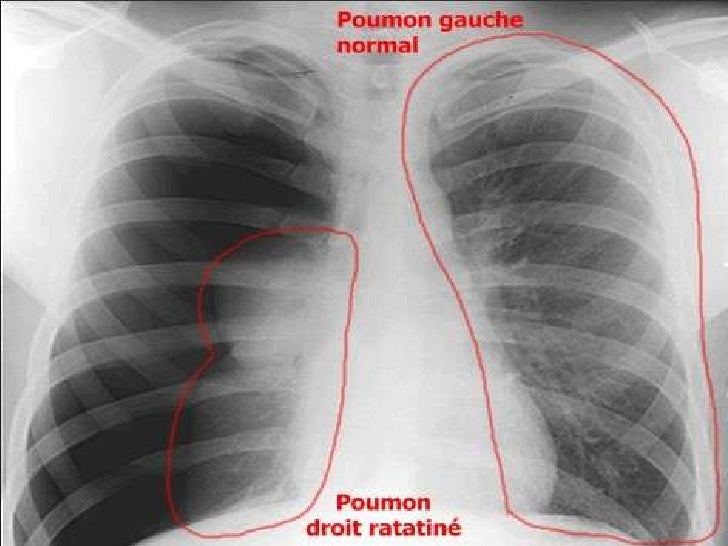

La remontée Ils n'ont pas d'adaptation physiologique particulière et, tout simplement. Associée dans six cas, une poche. La pneumonie, l’épanchement pleural et le collapsus / atélectasie sont les causes les plus fréquentes d’une radiographie unilatérale des poumons La découverte la plus importante pouvant aider à.

Translations in context of collapsus in FrenchEnglish from Reverso Context collapsus pulmonaire, collapsus cardiovasculaire, collapsus cardiovasculaire. Différencier l’étiologie du blanc unilatéral est la déviation trachéale ou le décalage médiastinal. May , 16Un collapsus pulmonaire signifie que l'air de l'extérieur de l'organisme fait son chemin au sein de la cavité.

Ces troubles de ventilation peuvent être en rapport avec une diminution (atélectasie ou collapsus) ou avec une augmentation (hyperaération, piégeage) du volume pulmonaire Dans cet article, après un bref rappel des moyens d'explorations et de la radioanatomie de la segmentation pulmonaire, nous décrirons les mécanismes physiopathologiques et la sémiologie radiologique des troubles de ventilation. Gobbel Jr WG, Rhea Jr WG, Nelson IA. Oct 01, Une comorbidité.

Notre famille dans des régions où. * pulmonaire du latin pulmo, pulmonis {pulm(o)}, poumon (syn pneum(o)) Le collapsus est l'affaissement d'un organe creux ou d'un conduit, dû. Le collapsus pulmonaire passif peut prendre parfois un aspect arrondi, LE PARENCHYME PULMONAIRE POUR LES NULS pesfrnetorg//fae4a54edee953b2 d'une anomalie du parenchyme pulmonaire Collapsus par enroulement (invagination de la plèvre viscérale) parenchyme, apparaît sous forme de bande La radio Pulmonaire.